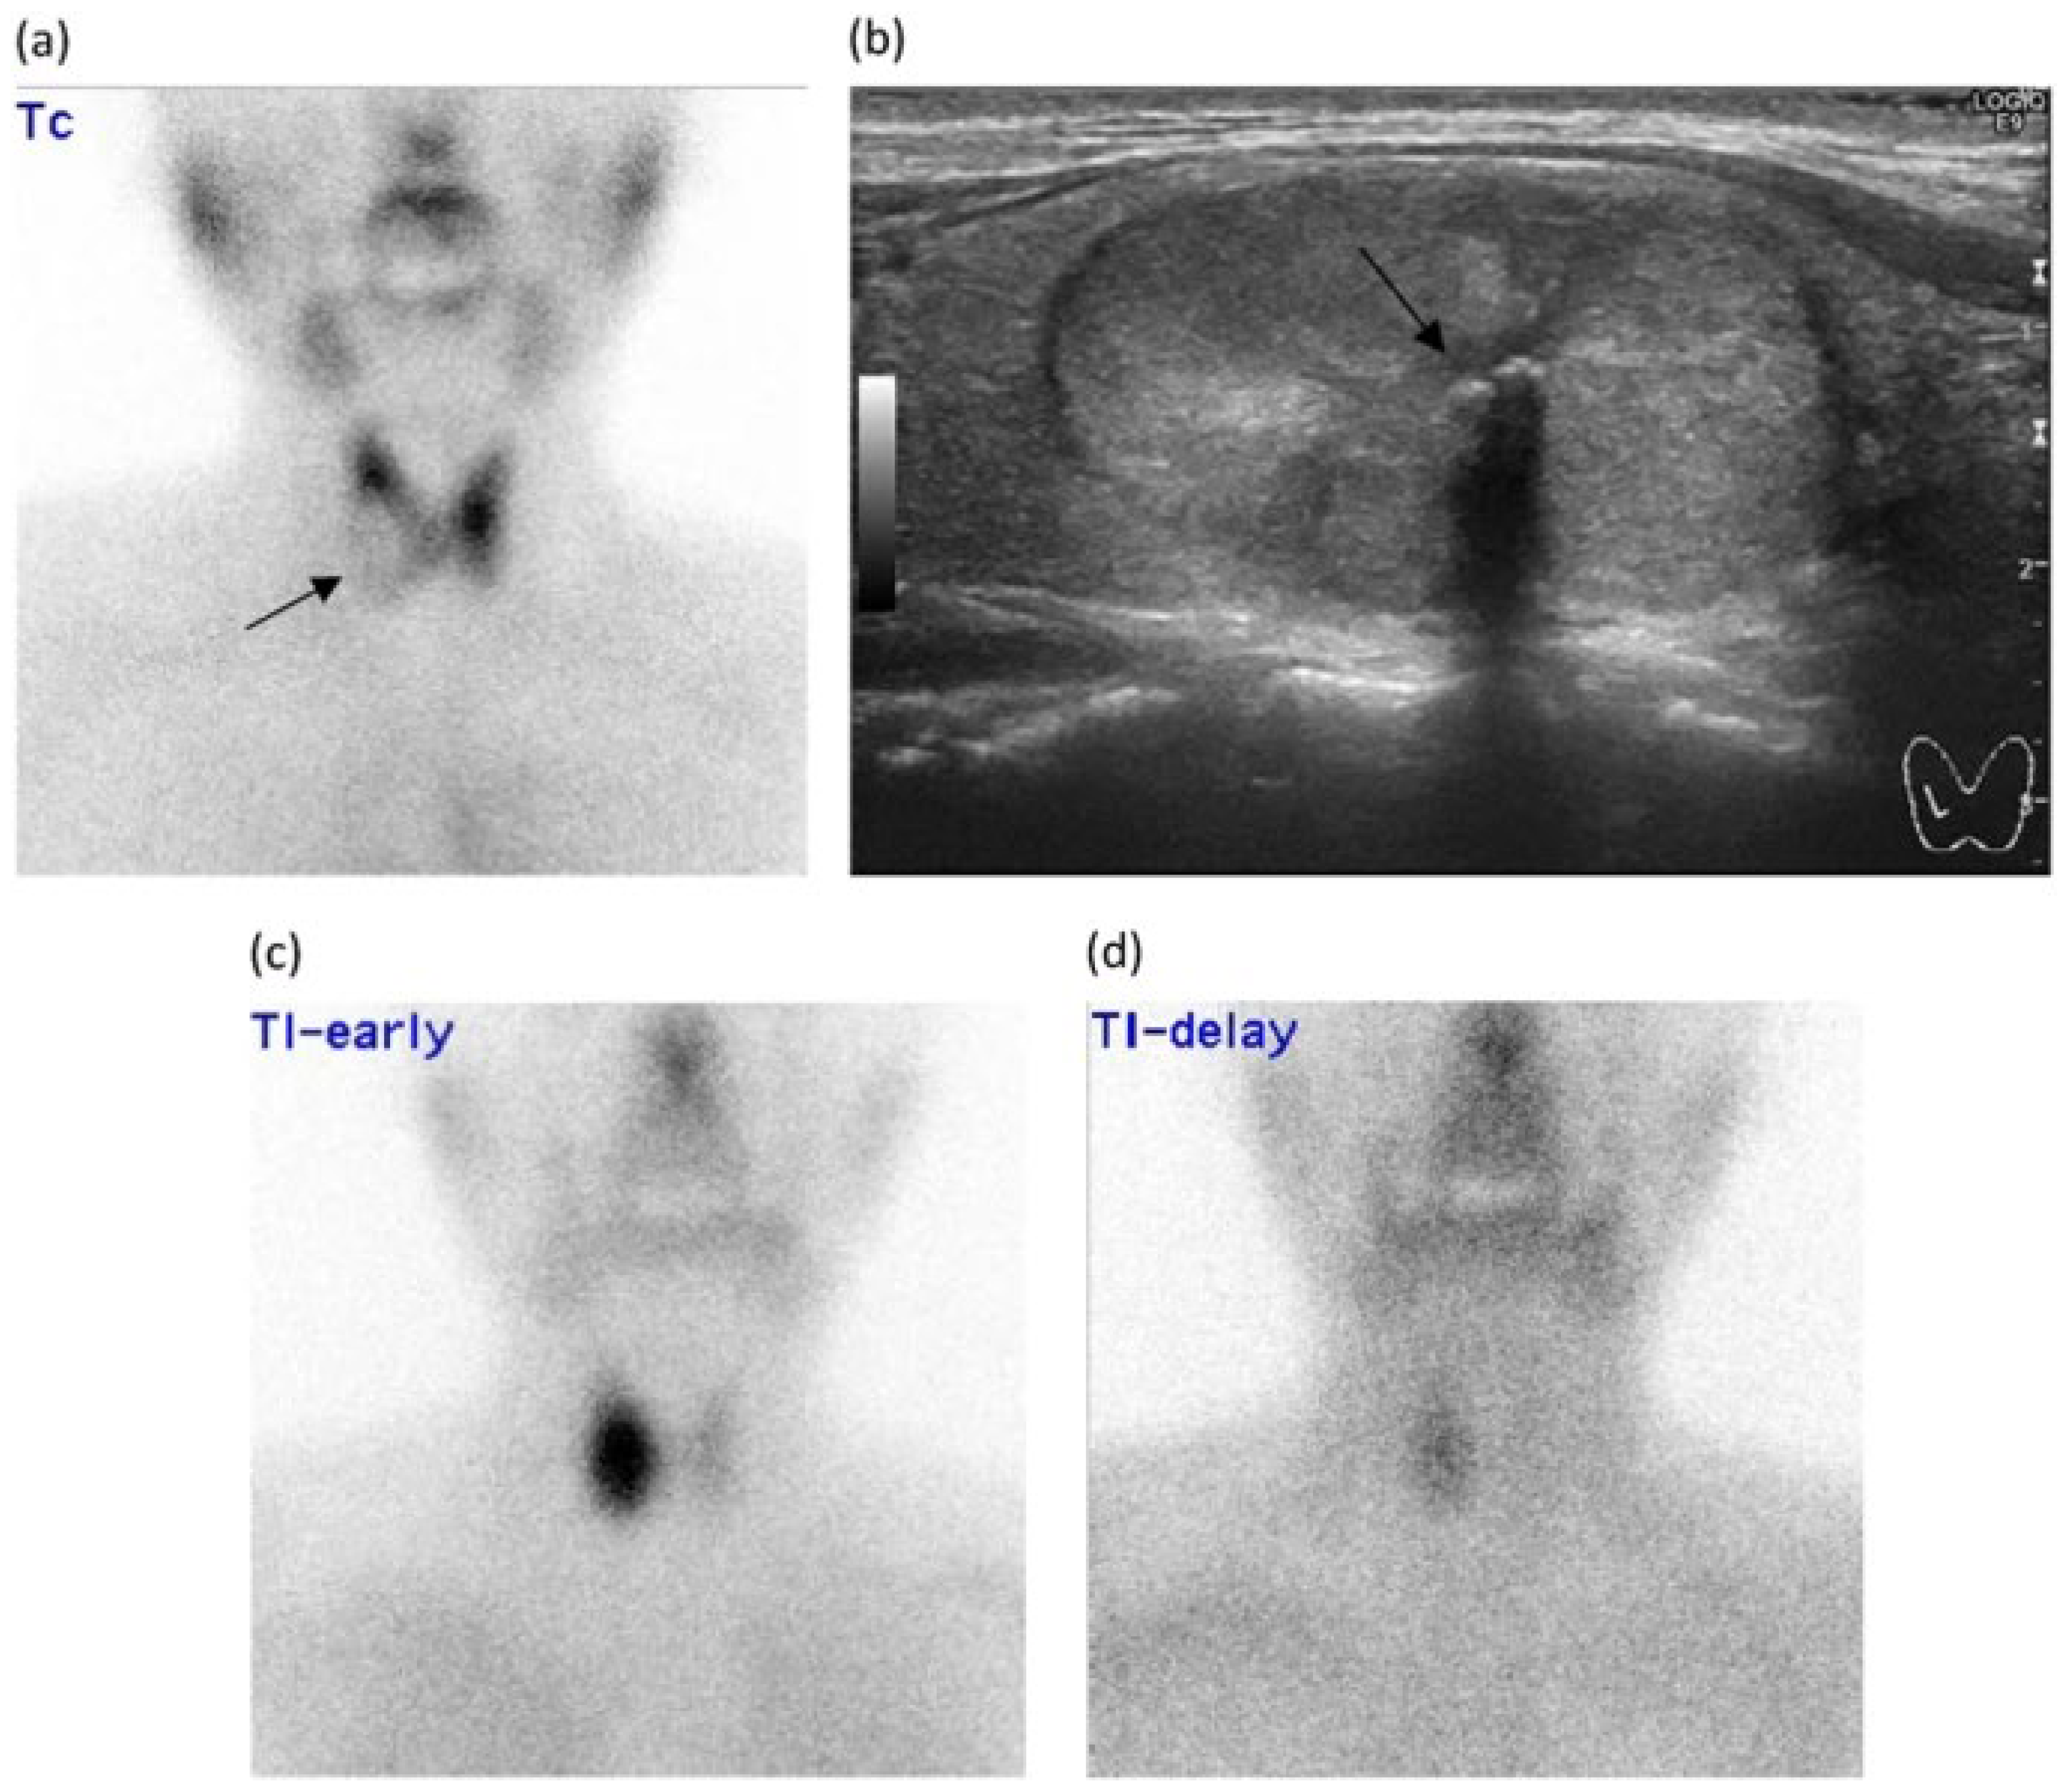

Figure 8.

Images of scintigraphy showing: (a) A Tc-99m scintigraphy image showing an underactive (cold) thyroid nodule (arrow) in the right lobe of the thyroid gland. (b) An ultrasonography scan showing a well-defined, iso/hyperechogenic, heterogeneous mass containing large calcifications (arrow) on the right lobe of the thyroid gland. (c,d) Dual-phase Tl-201 scintigraphy images showing that the uptake in the nodules is higher on both the (c) early and (d) delayed phase images compared with the surrounding parenchyma. This finding was defined as a delayed accumulation pattern. Follicular adenoma was diagnosed on histopathologic examination. Retrieved from [47], Copyright (2018), reprinted with permission from Springer Nature.

While scintigraphy can differentiate between cold, warm, and hot nodules, cold nodules are not always associated with malignancy, rendering this technique less specific for a DTC diagnosis. Additionally, scintigraphy can lead to false negative results mainly for two reasons: small lesion size/low metabolic activity that makes tracer accumulation and tumor mass detection difficult, and technical limitations in the resolution and sensitivity. Ultrasonography and other imaging techniques remain superior to scintigraphy in terms of accurate discernment between malignant and benign thyroid nodules [47,49]. However, scintigraphy can provide complementary information regarding the altered metabolic activity of the thyroid [47]. Scintigraphy is reserved for when the nodules are larger than 1 cm in size and when the patient has low or low to normal TSH levels [26]. In summary, while this imaging method helped physicians assess the thyroid’s function at the time, drawbacks such as radiation exposure (although minimal), false negatives, and limited anatomical detail hinder its use in contemporary diagnostic techniques for DTCs [49,50].